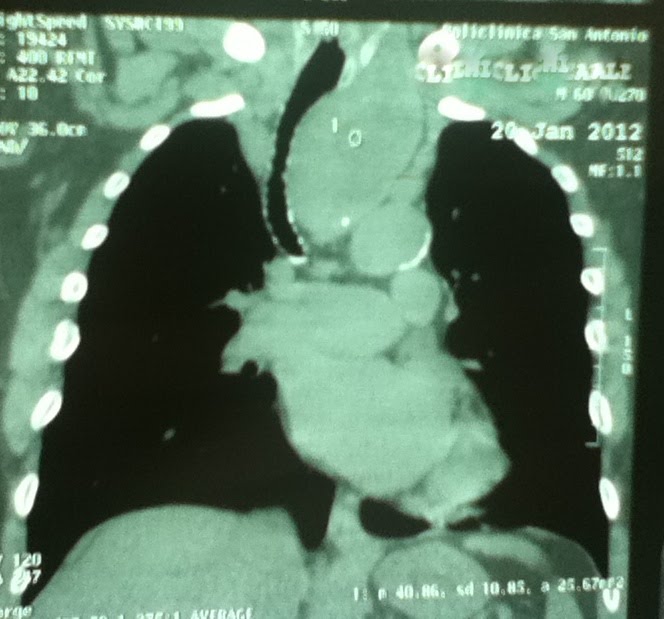

TCT de un paciente quien tenia tumoración en mediastino superior para traqueal izquierda, con desplazamiento de la traquea hacia la derecha, sin calcificaciones, bordes bien delimitado, con tumoracion costal derecha biopsiada con diagnóstico de carcinoma papilar de tiroides. Se extirpó la masa mediastinal por via cervical mas vaciamiento ganglionar para tratamiento Iodoradiactivo.